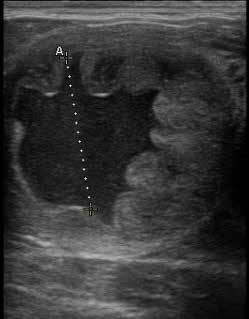

Seven days post-ovulation an embryo flush and collection was performed, using EMCARE embryo flush solution run through a low volume embryo filter. A day-7, grade-2 early blastocyst was recovered from this flush. This embryo was transferred within 30 minutes of collection into the owner’s recipient mare that had ovulated two days after the donor. Four days later, trans-rectal ultrasound revealed the recipient to be pregnant.

A cervical laceration repair Transrectal ultrasound image of a uterus following infusion of 500mL of Kerosene. Image taken 18 hours after infusion. The uterine lumen is profiled where the hyperechoic line is outlining the endometrial folds. Day 7 Grade 2 embryo